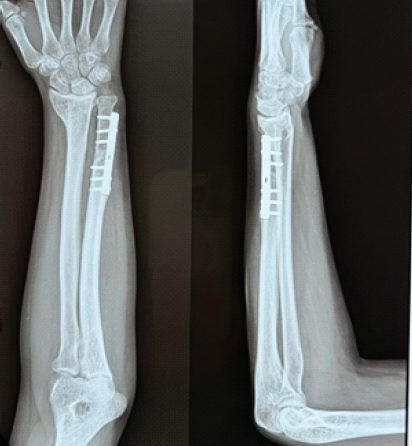

Ballistic Galeazzi Fractures: A Case Series

Timothy Westbrooks , Haley Tornberg , Kevin Heo , Olivia Jagiella-Lodise , Nicole Zelenski